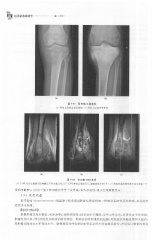

Page 278 - 医学影像诊断学